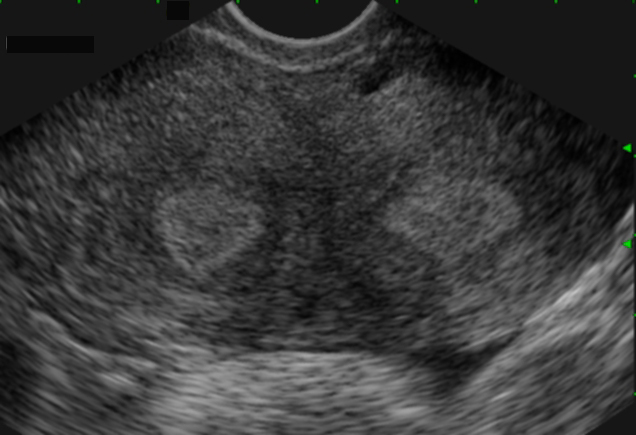

Utérus cloisonné (coupe transversale) (Cliché : Dr. C. TALMANT)